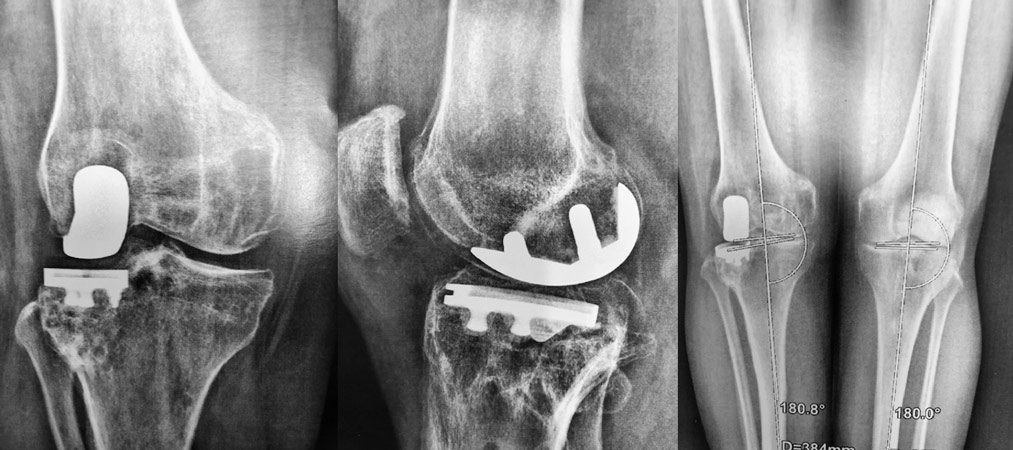

Arthrose externe, patiente jeune, genou en valgus (jambes en X), patiente jeune, on propose une ostéotomie pour ré-axer le genou.

Déformation du genou en valgus (jambes en X), femme jeune (45 ans), ancienne handballeuse aux jeux de Séoul ; le fémur et le tibia sont déformés. Handicap majeur.

On réalise une double ostéotomie de varisation lors de la même opération, fémorale et tibiale, fixées avec des agrafes métalliques.